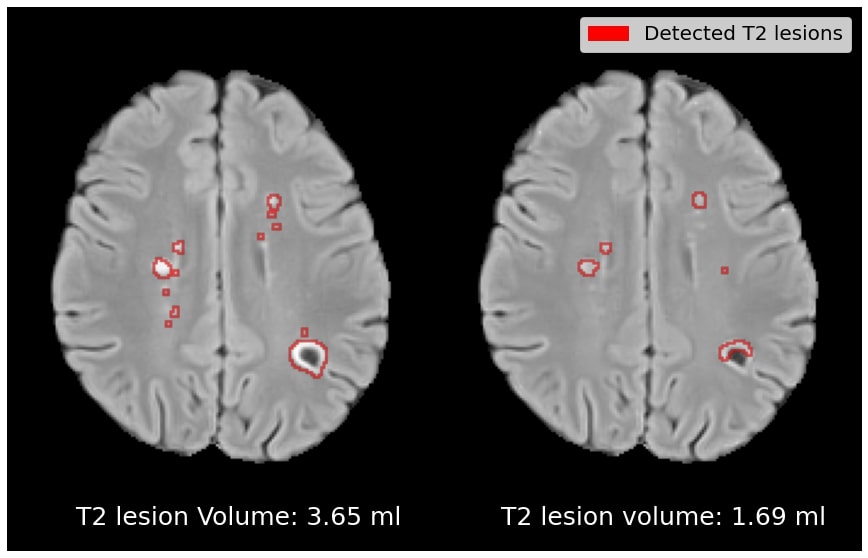

Target Class Similarity Quantitative results depicting the average T2 lesion volumes and Gad lesion prevalence for the reconstruction and generated counterfactual image are reported in Table 2. For comparison, we also include T2 lesion volume and Gad lesion prevalence statistics for real active and real inactive samples. In the top row, we see that the average T2 lesion volume of the reconstruction is relatively close to that of the real active samples. On the other hand, the average T2 lesion volume of the counterfactual is substantially lower, being closer to the T2 lesion volume of the real inactive subjects than the active subjects. A similar trend can be observed for Gad lesion prevalence, where the Gad prevalence of the generated counterfactual has dropped closer to the prevalence observed among real inactive subjects. Overall, these results show that the counterfactual images are realistic in terms of their ability to discover clinically established population-level predictive markers, without a priori knowledge of these markers. In this case, this leads to a reduction in baseline T2 lesions load and a removal of baseline Gad lesions from the counterfactual images.

Figure 4 depicts qualitative results for the effect on T2 and Gad lesion load. In (a), we show an example of a patient with above-average lesion load, with the counterfactual exhibiting a 79% drop in T2 lesion load. In (b), an active patient is shown with a below-average lesion load (i.e. an example that goes against the population-level trend), with the counterfactual exhibiting a 54% drop in T2 lesion load. In (c) and (d), the counterfactual images exhibit a complete suppression of Gad lesions. Overall, Gad lesions are suppressed to a much greater extent than T2 lesion suppression. This aligns with the statistics for real active and real inactive populations (see Table 2).